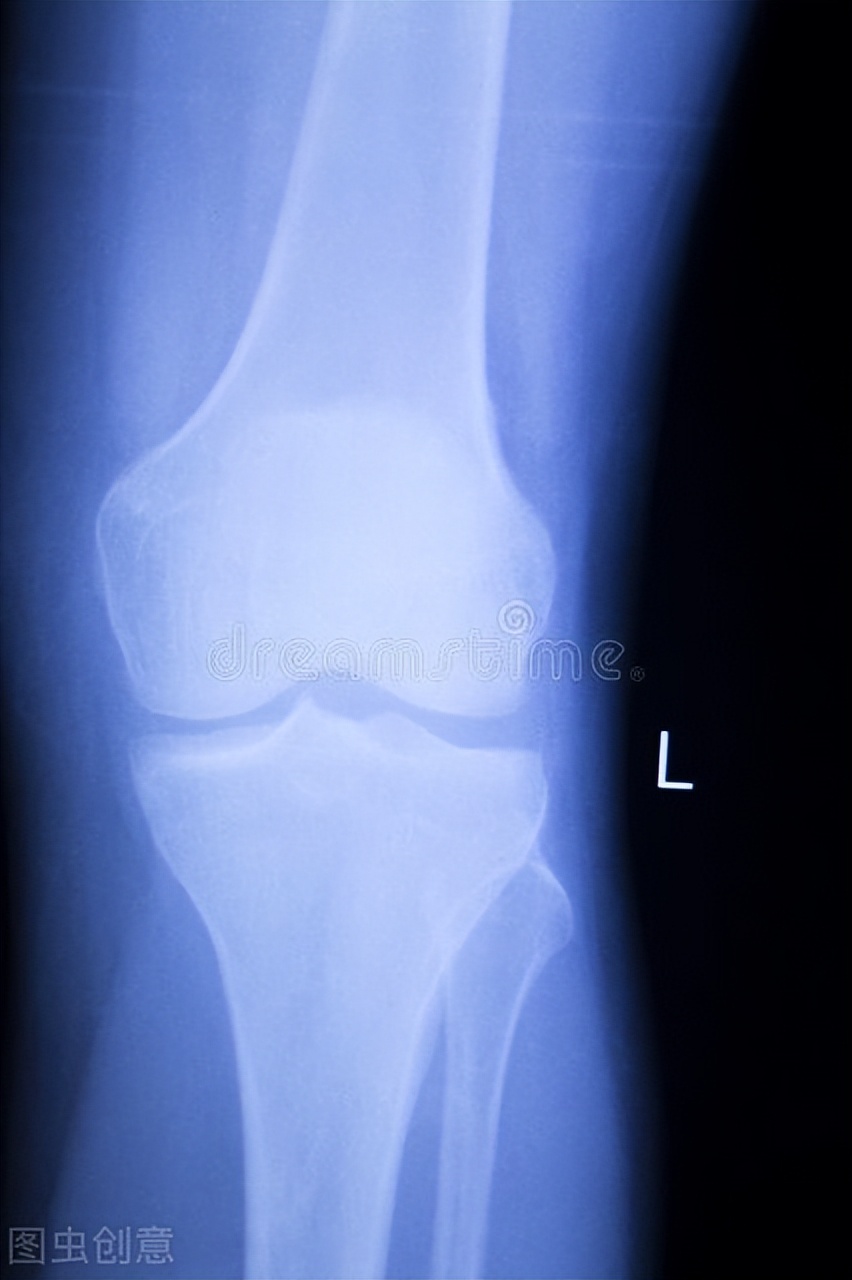

近日,一女子想要减肥,她看到很多运动博主每天跳绳几千几万个,于是她也跟着跟着每天跳绳4000下,坚持了一个月时间。有一天吴女士腿突然感到特别疼痛,于是去医院检查,检查结果显示半月板和韧带撕裂。

半月板损伤的临床症状有哪些?

半月板撕裂该如何治疗?